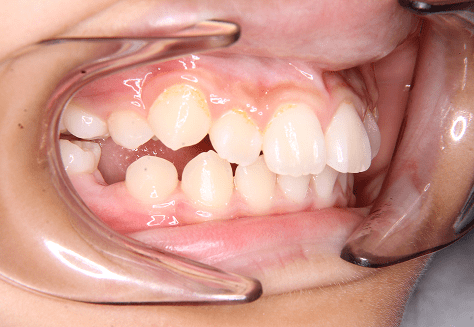

M.M

治療前

治療後

主訴

嚙み合わせが悪い。八重歯が気になる。

診断

叢生・反対咬合

年齢/性別

10代/女性

抜歯部位

非抜歯

使用装置

インビザラインファースト→インビザラインフェーズⅡ(部分的にワイヤーにて処置)

保定装置

上下ビベラリテーナー

基本料金

円ファースト時:450,000円

フェーズⅡ時:240,000円 -

診察料金

ファースト時:0円×16回

フェーズⅡ時:5,500円×9回

ワイヤー併用時:8,800円×2回 -

治療期間

2年7カ月